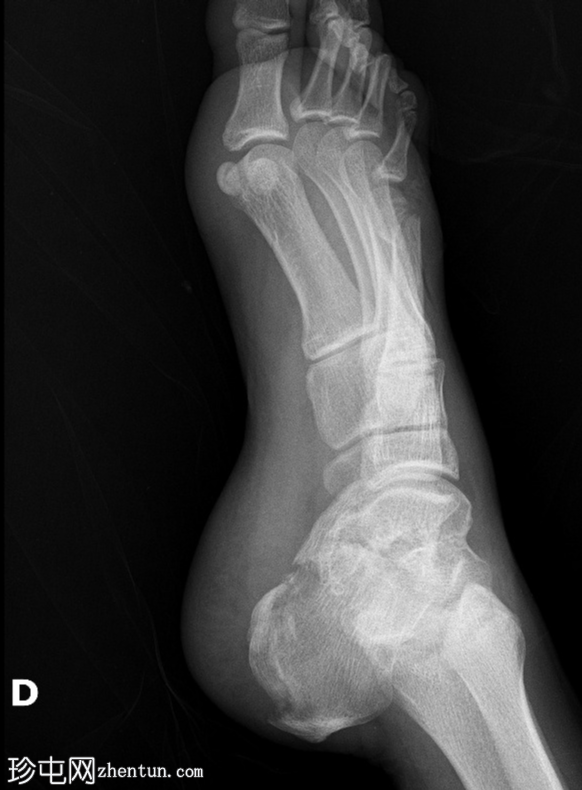

正位(放大)

第四趾近节指间关节(PIPJ)跖侧脱位。

第五趾近节指骨无移位骨折。

第五跖骨颈骨折伴跖侧移位(背侧成角)。

跟骨关节内骨折。